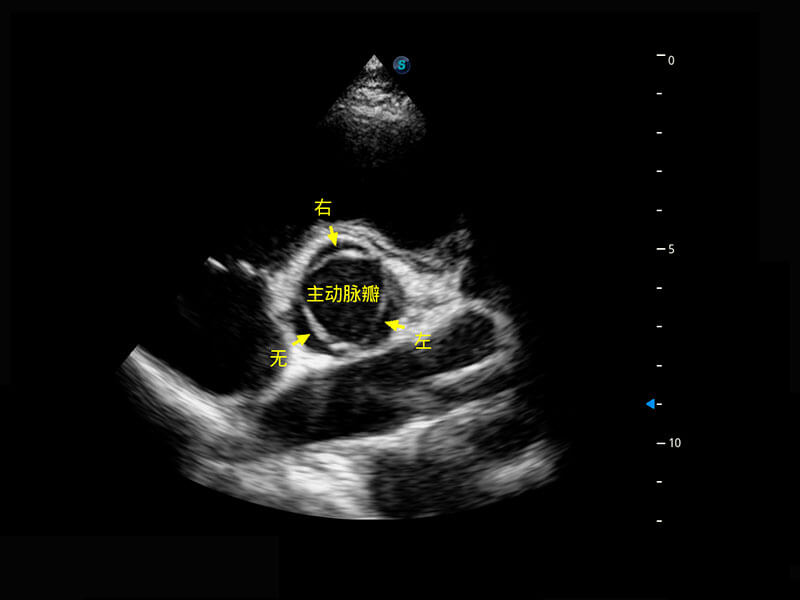

P60搭载一系列胎儿心脏成像技术,实现精细的胎儿心脏评估。

四腔切面

四腔心血流

胎心容积成像